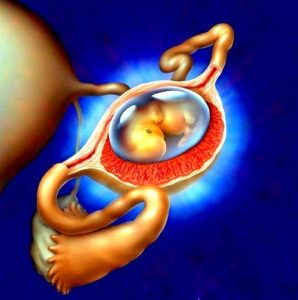

Існує дві стадії патології: прогресуюча і прервавшееся. Запліднена яйцеклітина при патологічній вагітності направляється в маткову трубу. Там вона прикріплюється. У жінки на ранньому терміні відбуваються ті ж зміни, які притаманні звичайній вагітності. Тому розпізнати патологію на ранньому терміні важко. Але плодове яйце зростає. Маткова труба розтягується до певного моменту і лопається. У цій ситуації жінку треба рятувати від кровотечі.

Перший місяць патологічна вагітність має схожість зі звичайною. У жінки відсутня менструація, спостерігається токсикоз, яйцеклітина зростає. По мірі її розвитку, вона збільшується в розмірах. Перші ознаки патології спостерігаються на строк від 5 до 8 тижнів, все залежить від того, в яке місце приліпилося плодове яйце:

Чи можна виносити дитину

Дитину виносить при позаматкової патології не можна. Ходять чутки про те, що народилася здорова дитина, який перебував у черевної порожнини жінки, але достовірності ці домисли так і не отримали.